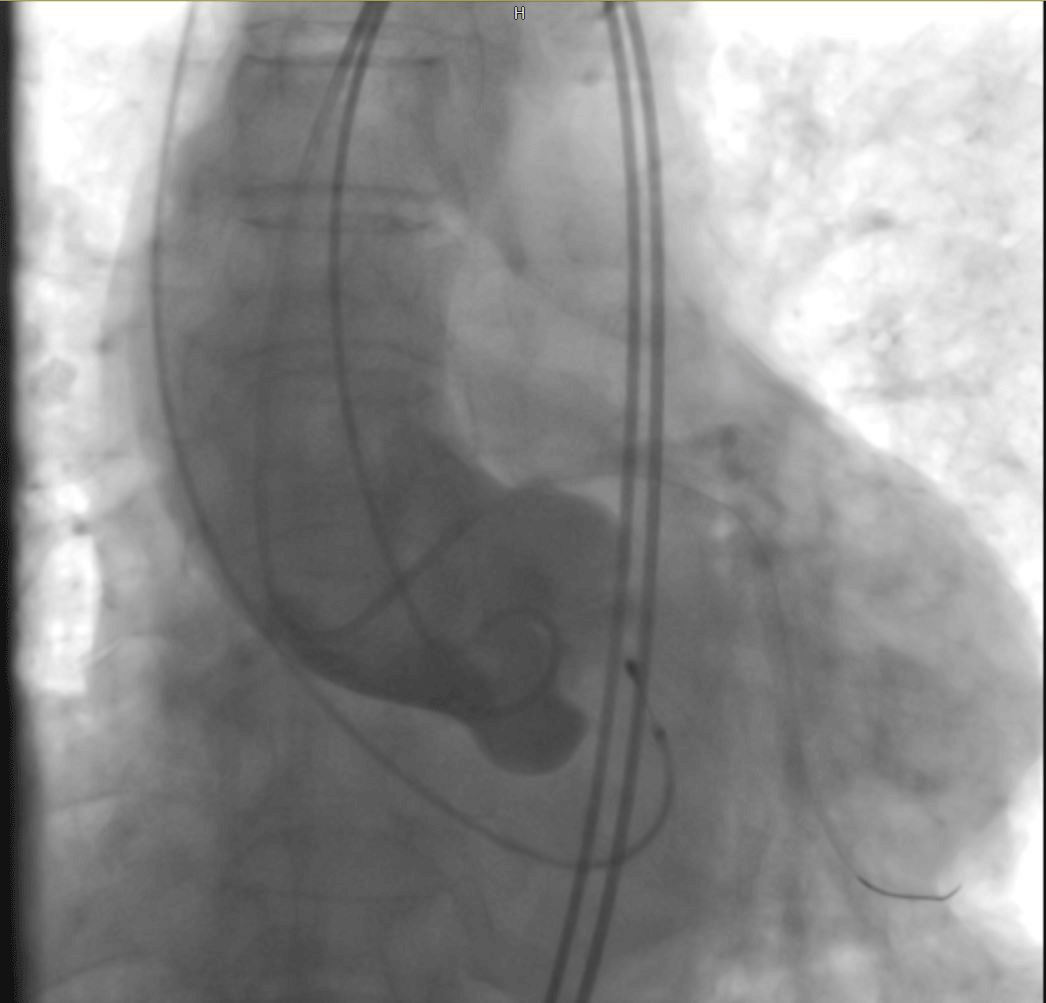

术后心电图提示无传导阻滞。